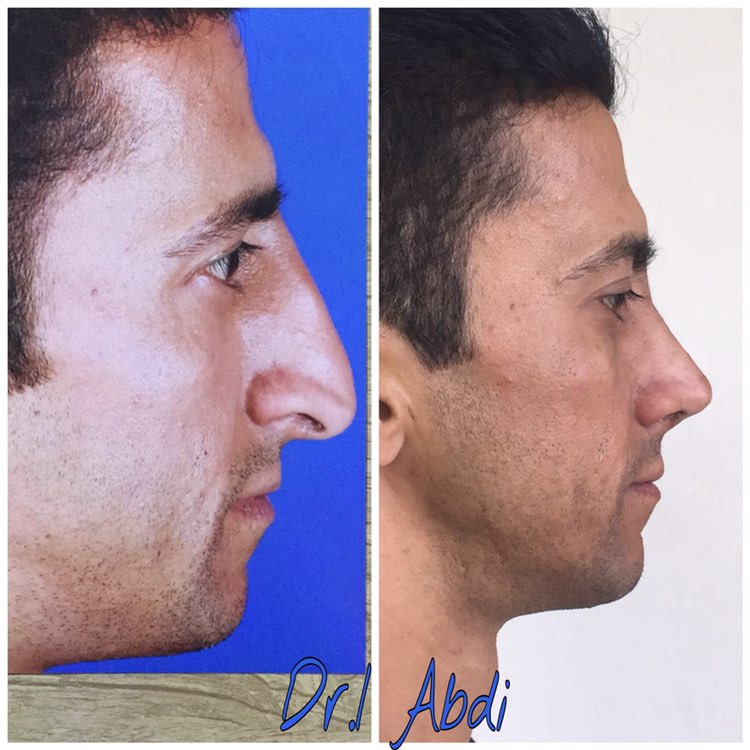

دکتر عیسی عبدی در رشت

دکتر عیسی عبدی در رشت

– متخصص جراحی فک , پلاستیک صورت و بینی

دکتر عیسی عبدی در رشت

جراحی فک , پلاستیک , صورت وبینی